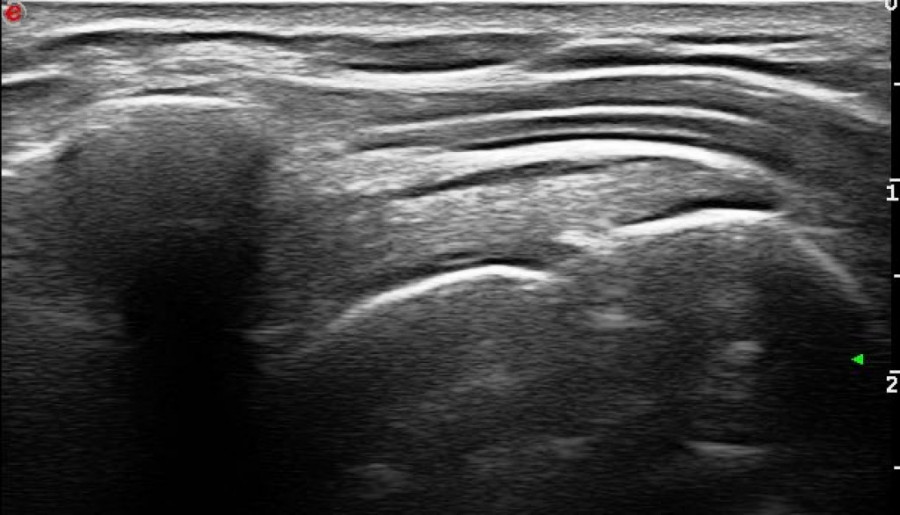

Foto: Promo fotoOrthokin terapija je neinvazivna metoda koja za lečenje koristi vlastitu krv pacijenta bez dodatka bilo kakvih hemijskih i stranih supstanci. U svetu se primenjuje preko 20 godina, a u Srbiji od 2012.godine. Efikasnost primene Orhtokin terapije do sada je dokazana u lečenju osteoartritisa kolena, kuka i drugih zglobova, artritisa, diskus hernije i lumboishialgije.

“Cilj naše Studije je bio da dokažemo da Orhtokin metodom može da se leči i hronična upala tetive ramena, takozvana Supraspinatus tendinopathy. Rezultati su pokazali da je potpuno bezbedna i efikasna, kako trenutno, tako i u smislu dužeg trajanja rezultata,” rekao je tokom razgovora s novinarima organizovanom na Insistitutu za reumatologiju prof. dr Damjanov.

Studija je sprovedena tako što je tokom tri meseca na jednoj grupi od ukupno 33 ispitanika, bez znanja pacijenta i lekara koji ga prati, primenjivana klasična terapija glikokortikoidima, a na drugoj Orthokin metoda. Lekar je beležio rezultate, kako se pacijent oseća, uspeh lečenja i eventualne probleme.